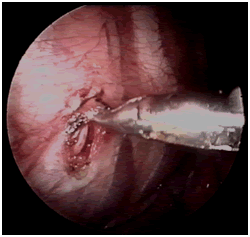

10mm鏡下右交感神經(jīng)鏈全長

電刀切開胸膜,找出并切斷胸交感神經(jīng)